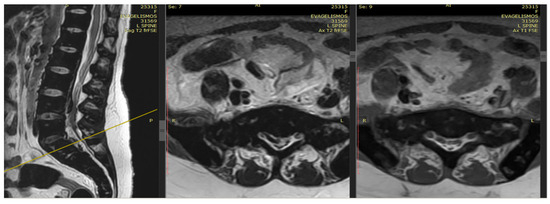

The patient noted a gradual improvement in neurological manifestations related to mobility and sensitivity. Upon discharge, she continued self-catheterization due to incomplete restoration of urination. Subsequently, the patient maintained subcutaneous iron chelation treatment with deferoxamine at a dosage of 80 mg/kg. Severe aplasia occurred two months after initiating hydroxyurea, leading to the discontinuation of both deferiprone and hydroxyurea until complete hematological recovery. Despite efforts to reintroduce hydroxyurea, the patient experienced aplasia again, prompting the decision to permanently cease this medication. Six months after the initial symptom onset, MRI findings indicated a reduction in mass and iron deposition (Figure 3 and Figure 4). The patient continued intensive iron chelation therapy with a combination of deferiprone and deferoxamine, resulting in a decreased iron load. Transfusions were maintained every 15 days with the goal of achieving hemoglobin levels above 10 g/dL. The patient achieved complete neurological recovery in the sensory and motor aspects, with only a minor improvement noted in neurogenic bladder dysfunction. Despite our patient experiencing severe myocardial iron overload, she maintained satisfactory systolic function in both the left and right ventricles. There were no observed valvular or conduction abnormalities, and the volume overload resulting from hypertransfusion did not adversely affect her overall cardiac function.

Figure 3.

The MRI findings six months after the first appearance of symptoms showed a decrease in mass and iron deposition.